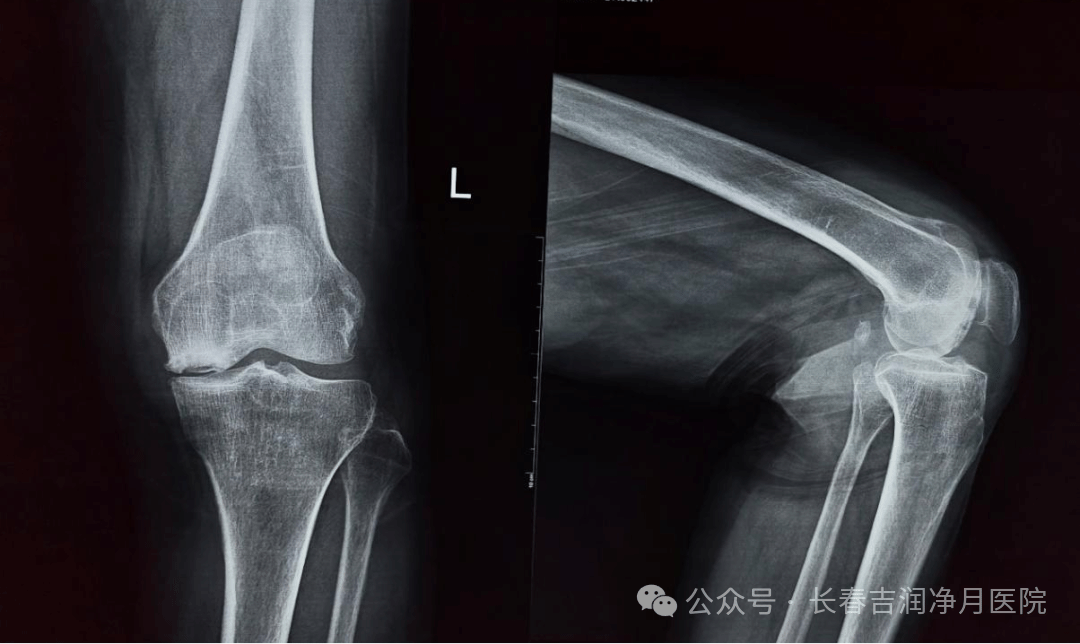

12月17日上午,由吉大一院骨关节科刘建国教授主刀,在麻醉科麻海春教授团队配合下,为患者实施了手术。术中见关节软骨大面积磨损,滑膜增生,骨赘增生。刘建国教授采用精准力线重建技术,结合术前规划,实现截骨误差≤0.5mm,植入的骨水泥 PS 假体(后稳定型)具有耐磨性强、贴合人体解剖结构的优势。术中测试显示关节稳定,屈曲活动度良好(0°-120°)。手术历时60分钟,术中出血量仅 50ml,未输血。缝合伤口前,采用关节周围“鸡尾酒”注射镇痛,这些措施有助于术后疼痛管理和早期功能锻炼。术后X线显示膝关节假体位置达到预期。